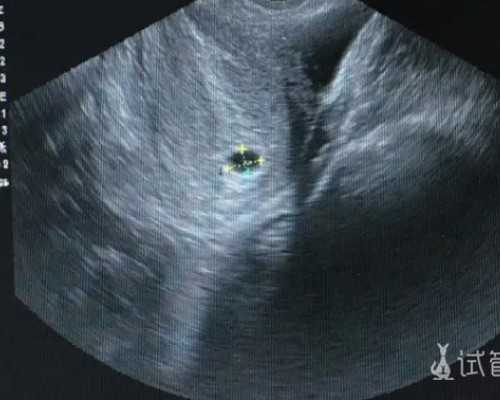

试管是一个繁琐而又重要的步骤,有许多人问试管前期检查能同房吗?答案是肯定的,但是在此之前需要进行一些准备工作。什么是试管前期检查?试管前期检查是指患者按照医嘱进行的一系列检查,这些检查用于确定患者的生育能力,以及评估病情。它包括血液检查、宫......